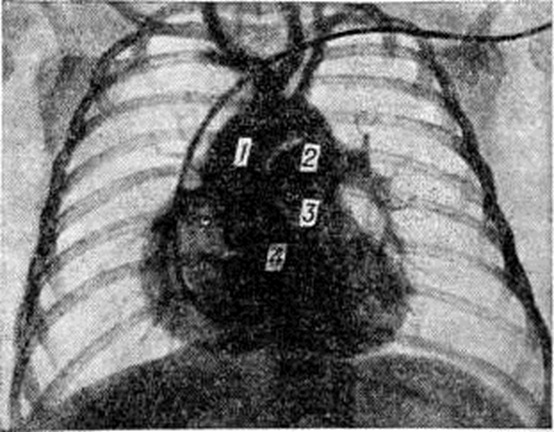

Относительно благоприятное состояние у большинства остальных больных может продолжаться несколько месяцев и обеспечивается существующей у новорожденных естественной полицитемией, наличием открытого артериального протока (смотри полный свод знаний) и относительно небольшим сопротивлением кровотоку, связанным со стенозом лёгочного ствола. Выраженные симптомы порока обычно развиваются в возрасте 4 — 6 месяцев У больных появляются отдышка (смотри полный свод знаний) и цианоз, усиливающиеся при физической нагрузке. Вследствие хронический гипоксемии развивается деформация концевых (дистальных фаланг пальцев в виде барабанных палочек (смотри полный свод знаний: Барабанные пальцы), ногти приобретают форму часовых стёкол. Увеличивается сеть венозных сосудов подкожной клетчатки. Выраженность этих признаков и полицитемия возрастают по мере увеличения объёма венозного сброса крови и степени цианоза. Дети начинают отставать в физическом развитии. Для отдыха занимают характерное положение на корточках. Наиболее грозными проявлениями порока являются приступы одышки, возникающие в результате внезапно развивающегося спазма артериального конуса правого желудочка. Во время приступа резко усиливаются одышка, цианоз, тахикардия (смотри полный свод знаний). Иногда приступ заканчивается развитием гипоксической комы (смотри полный свод знаний: Кома). При пальпации грудной клетки над областью сердца определяется грубое систолическое дрожание и усиленный верхушечный толчок. Границы сердца расширены умеренно. При аускультации тоны сердца громкие, первый тон на верхушке усилен. Наиболее характерным является ослабление второго тона над лёгочным стволом. При фонографическом исследовании второй тон над этой областью сердца расщеплен и его лёгочный компонент значительно снижен или отсутствует. Над сердцем выслушивается грубый систолический шум с максимальным звучанием в третьем-четвёртом межреберье слева от грудины. Шум проводится на сосуды шеи и на спину. На фонограмме зона шума имеет ромбовидную форму и занимает всю систолу (смотри полный свод знаний: Фонокардиография). В случаях, когда степень стеноза приближается к атрезии лёгочного ствола, интенсивность шума бывает минимальной или же он не выслушивается вообще. У больных с выраженным коллатеральным кровообращением над лёгкими прослушивается систолодиастолический шум в межлопаточном пространстве. На ЭКГ у всех больных отмечается отклонение электрической оси сердца вправо, а в грудных отведениях — признаки перегрузки правого желудочка и предсердия (смотри полный свод знаний: Электрокардиография). Рентгенологические исследование имеет важное значение для диагностики Фалло тетрада При этом лёгочные поля имеют обеднённый артериальный сосудистый рисунок, в прикорневой зоне нередко отмечаются хаотично расположенные тени коллатеральных сосудов. Тень сердца в переднезадней проекции у большинства больных увеличена незначительно, но имеет достаточно специфическую конфигурацию, напоминающую деревянный башмачок с закруглённой, приподнятой над диафрагмой верхушкой и западением в области лёгочного ствола (рисунок 1, а). В косых проекциях выявляются признаки увеличения правых и относительное уменьшение левых отделов сердца. Тень левого желудочка во второй косой проекции выглядит как небольшое выбухание с крутой кривизной (симптом шапочки) по задней поверхности сердечной тени (рисунок 1, б). Важное значение для окончательной диагностики Фалло тетрада, определения степени нарушения гемодинамики и уточнения анатомических изменений имеют дополнительные исследования — катетеризация полостей сердца (смотри полный свод знаний: Катетеризация сердца) и ангиокардиография (смотри полный свод знаний). Результаты этих исследований необходимы для решения двух важных практических вопросов — определения показаний к хирургическому лечению и выбор оптимального типа операции. Давление в лёгочном стволе при Фалло тетрада не превышает 10—20 миллиметров ртутного столба, а в правом желудочке оно равно давлению в левом желудочке или давлению в системной артерии. По изменению характера кривой в момент перехода кончика зонда из отдела с низким давлением в полость правого желудочка можно определить место расположения и степень выраженности стеноза. При клапанном стенозе регистрируется резкий перепад давления между лёгочным стволом и правым желудочком. Для инфундибулярного стеноза характерно сниженное давление на некотором протяжении кривой правожелудочкового давления. При комбинированном стенозе выявляется два уровня перепада давления. Определяя насыщение крови кислородом из проб, взятых в полостях сердца и системной артерии, устанавливают направление и величину внутрисердечного сброса, минутный объём правого и левого сердца. Ангиокардиографию необходимо выполнять в двух проекциях: переднезадней и боковой. Рентгеноконтрастное вещество вводят через катетер, расположенный в полости правого желудочка. На первых же кадрах ангиограммы выявляется основной признак порока — одновременное поступление рентгеноконтрастного вещества в лёгочный ствол и аорту (рисунок 2). Наряду с этим выявляется стеноз лёгочного ствола, который наиболее чётко может быть определён в боковой проекции. Когда при анализе ангиограмм, выполненных таким путём, возникают подозрения на существование дополнительных уровней стеноза на протяжении лёгочного ствола, необходимо проведение дополнительного исследования в аксиальной проекции. Лечение Фалло тетрада только хирургическое. Тауссиг (Н. В. Taussig) в 1944 год предложила для увеличения лёгочного кровотока и снижения гипоксемии накладывать анастомоз между ветвями аорты и лёгочного ствола. В 1944 год Блелок (A. Blalock) разработал и успешно выполнил в клинике операцию наложения анастомоза между левыми подключичной и лёгочной артериями. В последующем было предложено много вариантов операций. Наиболее эффективными оказались предложения Поттса (VV. J. Potts, 1946) — анастомоз бок в бок между нисходящей частью аорты и левой лёгочной артерией и Уотерстона (D. J. Waterston, 1962) — анастомоз между восходящей частью аорты и правой лёгочной артерией. Р. Брок (1948) предложил устранять стеноз лёгочного ствола специальным инструментом, вводимым в полость правого желудочка через прокол его передней стенки. Радикальную коррекцию порока, включая устранение стеноза и закрытие межжелудочкового дефекта, первым в условиях гипотермии (смотри полный свод знаний: Гипотермия искусственная) выполнил Скотт (Н. W. Scott) в 1954 год, а первый успешный результат получил Лиллихей (С. W. Lillehei, 1955), который для выполнения операции применил экстракорпоральное кровообращение. В том же году Кирклин (J. W. Kirklin) начал выполнять радикальные операции в условиях, когда и циркуляция и оксигенация крови осуществлялась с помощью аппарата искусственного кровообращения (смотри полный свод знаний: Искусственное кровообращение). Тем самым он завершил создание современной методики операции. Разработаны паллиативные и радикальные операции. Показания к ним определяются в зависимости от возраста и состояния больных. Радикальная операция считается методом выбора. Паллиативные операции, направленные на увеличение лёгочного кровотока и снижение гипоксемии, в настоящий, время выполняются у детей раннего возраста и больных, находящихся в очень тяжёлом состоянии. Но и в этих случаях они являются лишь первым этапом лечения Фалло тетрада В последующем при улучшении общего состояния производят радикальную коррекцию. Среди многих типов паллиативных операций практическое значение сохраняют две. 1. Операция Блелока — Тауссиг, которая обязательно выполняется на стороне, противоположной расположению дуги аорты. Грудную клетку вскрывают боковым доступом в четвёртом межреберье. После выделения левой подключичной артерии и левой лёгочной артерии в корне лёгкого между ними накладывают анастомоз по типу конец в бок (рисунок 3). 2. Операцию Уотерстона в модификации Кули (D. A. Cooly) осуществляют правосторонним переднебоковым доступом в четвёртом межреберье. Внутриперикардиально выделяют правую лёгочную артерию и восходящую часть аорты. Участок задней поверхности аорты пристеночно отжимают зажимом, которым одновременно пережимают и проксимальный конец правой лёгочной артерии (рисунок 4). Дистальный конец артерии перекрывают турникетом под верхней полой веной. В прилегающих отделах сосудов делают разрез и накладывают анастомоз бок в бок диаметром 4—5 миллиметров. Преимущество этих операций по сравнению с другими видами паллиативных вмешательств состоит в их высокой (на протяжении 3—5 лет) эффективности. Кроме того, они меньше, чем другие, затрудняют выполнение в последующем радикальной операции. Послеоперационная летальность составляет 2—5%. Радикальную операцию выполняют на открытом сердце в условиях искусственного кровообращения (смотри полный свод знаний) и кардиоплегии (смотри полный свод знаний). Устраняют клапанный стеноз, тщательно иссекают все мышечно-фиброзные структуры, образующие препятствия на пути поступления крови из правого желудочка в малый круг кровообращения. Гипоплазированные участки правого желудочка, фиброзного кольца, лёгочного ствола и его ветвей расширяют до должных размеров путём вшивания заплат из аутоперикарда или синтетической ткани. Дефект межжелудочковой перегородки закрывают заплатой, подшиваемой к его краям непрерывным или П-образными швами. Послеоперационная летальность колеблется от 8 до 15% в зависимости от тяжести исходного состояния больного и объёма произведённой реконструкции, Правильно выполненная операция обеспечивает нормализацию гемодинамики и хорошие отдалённые результаты. Смотри полный свод знаний: Лёгочный ствол, Пороки сердца врождённые, Сердце.